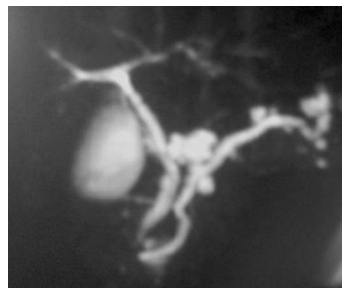

Um paciente de 62 anos de idade, etilista, assintomático, fez exames de ultrassom, que revelaram lesões pancreáticas císticas. Realizou, também, uma colangiopancreatografia, uma ressonância e exames laboratoriais. No exame de sangue, amilase e lipase normais e CEA e Ca19.9 dentro do limite

A imagem acima corresponde ao exame de

Uma paciente de 69 anos de idade, portadora de diabetes tipo 2, hipertensão arterial e hipotireoidismo, com história de IAM em 2017, apresenta quadro de icterícia progressiva, colúria, acolia, dor abdominal em hipocôndrio direito e perda ponderal de 5 kg no último mês, com inapetência e queda do estado geral. Aos exames, Hb 9 g/dL, leucócitos 12.000/mm3 , amilase 80 U/L, TGO 250, TGP 190, bilirrubina total 11 mg/dL, bilirrubina direta 9,5 mg/dL, fosfatase alcalina 320 mg/dL, gama GT 400 mg/dL e PCR 2,5 mg/dL. Ao exame físico, dor à palpação de epigástrio e hipocôndrio direito, sem DB. Realizou uma ultrassonografia de abdome, que mostrava dilação de vias intra e extra-hepáticas, com espessamento de vesícula biliar. Complementou a investigação com ressonância magnética. Mostrou a imagem a seguir.